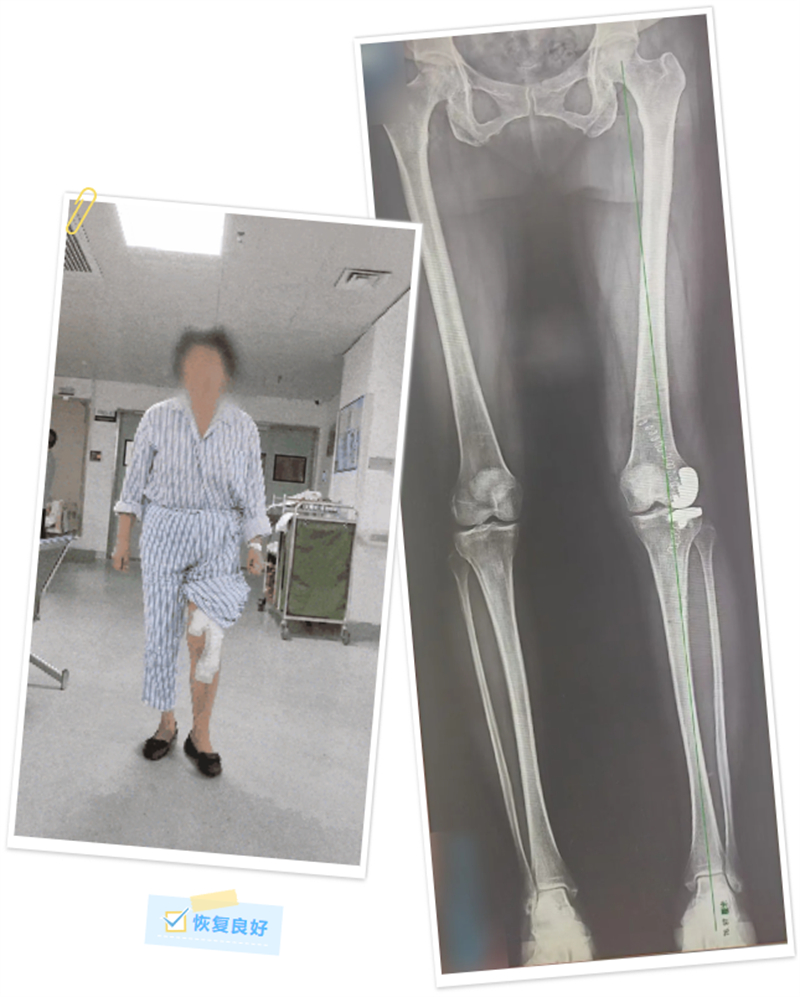

术前,手术团队将患者的下肢CT数据录入机器人系统后,运用计算机对假体的位置及型号参数进行了详细的规划和模拟,术中再次对患者的下肢力线及软组织张力进行了实时校对和调整。在机械臂连接的专用工具辅助下,最终成功将假体植入,并获得了较好的软组织张力平衡和活动度,同时纠正了患者的下肢力线。

术后,覃女士恢复良好,还送来了写着“医术精湛、医德高尚”的锦旗表示感谢。